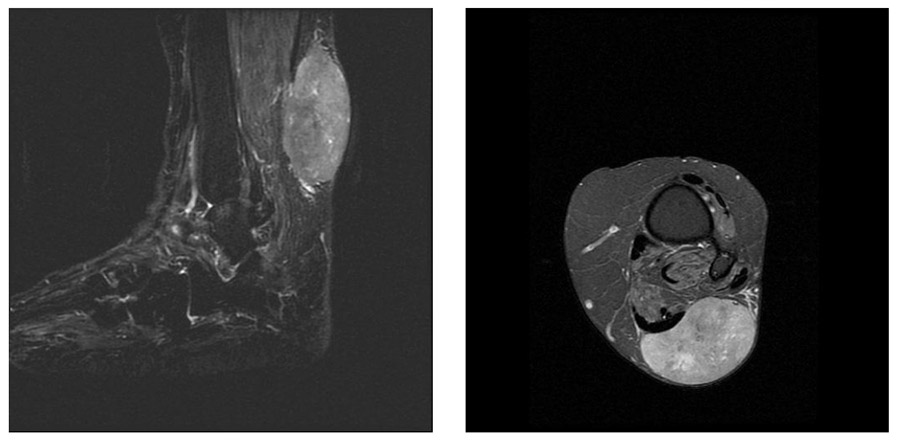

Ameliyat Öncesi: MR’da ayak bileği arka yüzde yerleşimli, heterojen yumuşak doku tümörü görülmekte